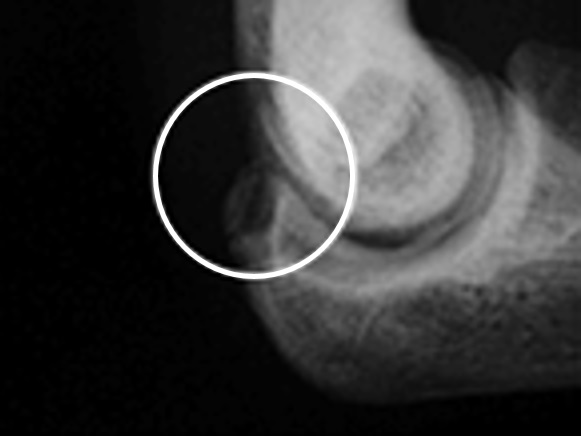

Thrower’s elbow is a sports disorder that is caused by baseball throwing, particularly overuse, which occurs in growing pitchers, and is mainly characterized by throwing pain in the throwing elbow of the medial side (Fig. 1), the outer side (Photo 1), and the elbow head (Photo 2). Symptoms often develop gradually and become chronic, so attention should be paid to elbow pain. The acceleration phase (acceleration) of throwing movements takes place in elbow flexion, valgus, and forearm supination. In the medial type, traction is exerted by the pronator flexor in throwing on the inside of the elbow, stretching the pronator muscles, the medial collateral ligaments, and the ulnar nerve, causing micro-damage inside the elbow. In severe cases, the medial epicondyle of the humerus develops avulsion fractures due to traction. In the lateral type, pressure is applied to the capitulum of the humerus and radius on the lateral side of the elbow, resulting in osteochondritis dissecans, with bone necrosis, defects, and loose bodies. The posterior type is in an elbow extension position during deceleration (follow-through), and traction forces are applied to the olecranon of the ulna, resulting in changes such as avulsion and stress fractures.

Photo 2 Olecranon type: olecranon of the ulna showing bony dehiscence

These symptoms can be accompanied by bony changes on X-ray. In the medial type, bone thickening of the medial epicondyle of the humerus, epiphyseal line separation, and free bone in the pronator region are observed; in the lateral type, bone deformation, defect, and a free bone fragment of the capitulum of the humerus and head of the radius are observed; and in the posterior type, fissure fracture and stress fracture of the olecranon of the ulna are observed.